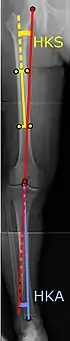

![]() |

Ángulos comúnmente medidos antes de la cirugía de reemplazo de rodilla: |

Para indicar el reemplazo de rodilla en caso de osteoartritis, su clasificación radiográfica y la gravedad de los síntomas deben ser sustanciales. Dicha radiografía debe consistir en radiografías en carga de ambas rodillas: AP, lateral y 30 grados de flexión. Es posible que las proyecciones AP y lateral no muestren un estrechamiento del espacio articular, pero la vista en flexión de 30 grados es más sensible al estrechamiento. También se utilizan proyecciones de longitud completa para ajustar la prótesis para proporcionar un ángulo neutro para la extremidad inferior distal. Dos ángulos utilizados para este propósito son:

- Ángulo cadera-rodilla-eje (CRE),[8] un ángulo formado entre una línea que pasa por el eje longitudinal de la diáfisis femoral y su eje mecánico, que es una línea desde el centro de la cabeza femoral hasta la muesca intercondilar de la diáfisis femoral. fémur.[10]

- Ángulo cadera-rodilla-tobillo (CRT),[9] que es un ángulo entre el eje mecánico femoral y el centro de la articulación del tobillo.[10] Normalmente se encuentra entre 1.0° y 1.5° de varo en adultos.[11]